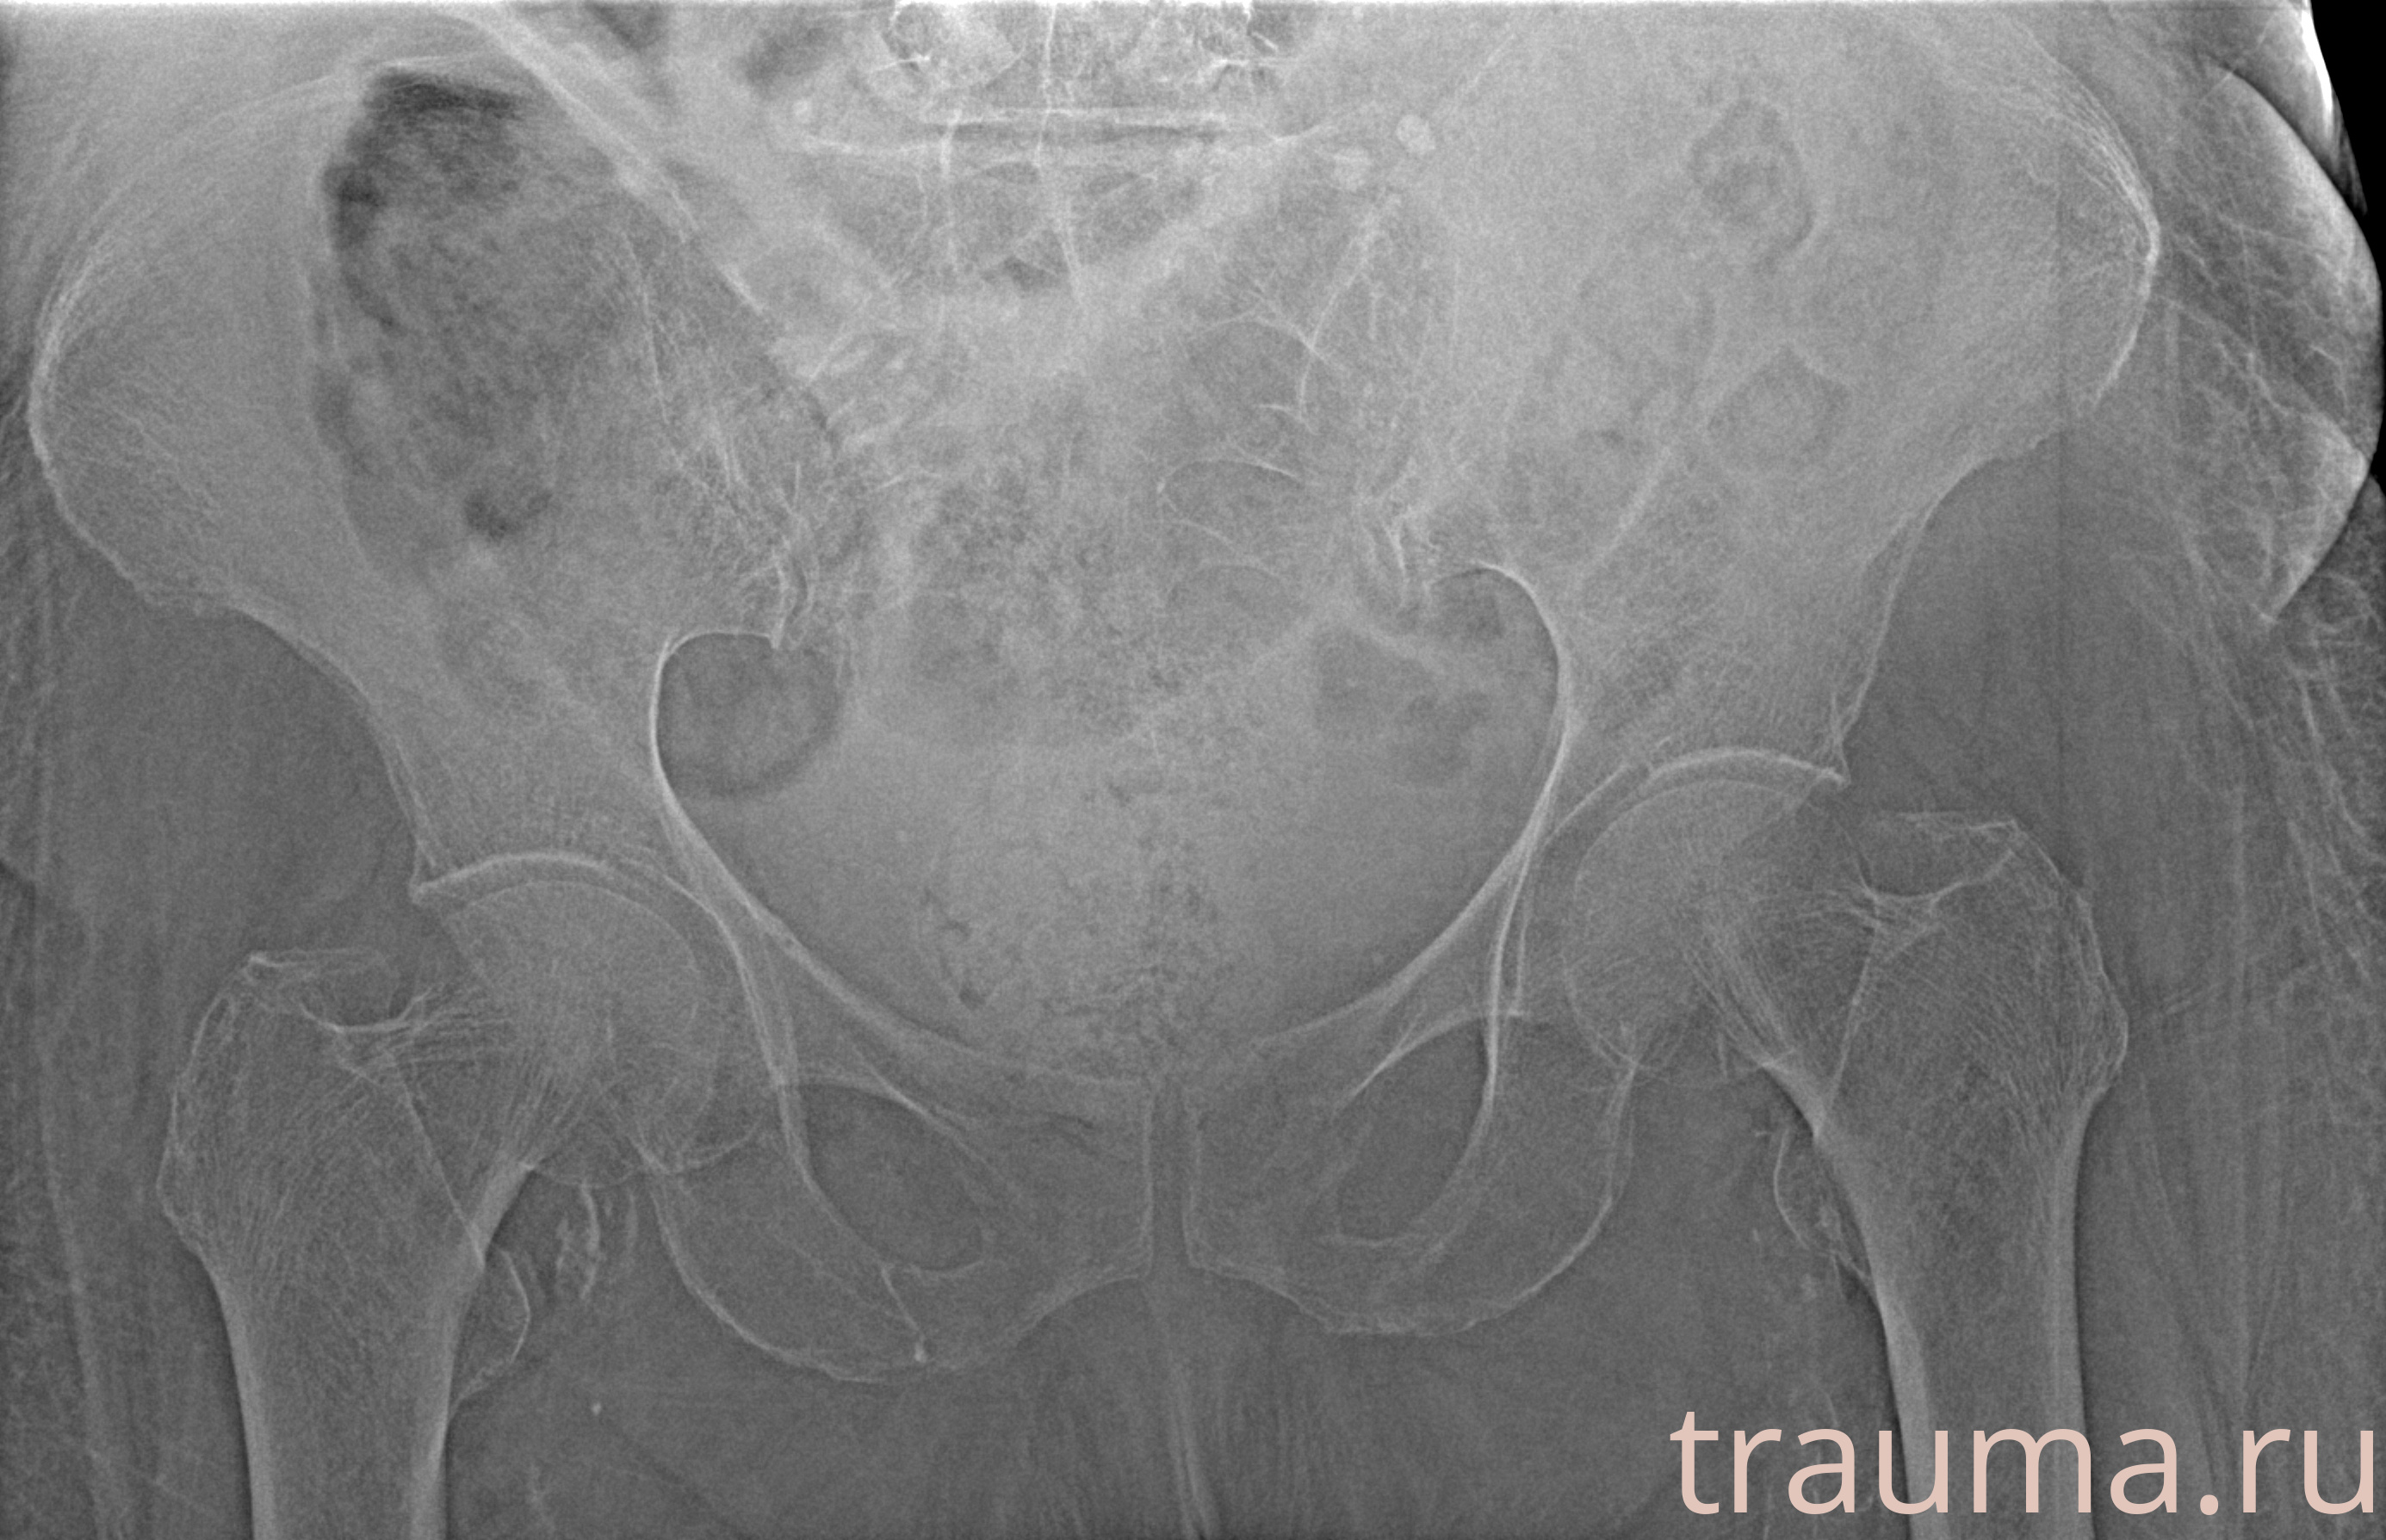

Рентгенограммы

Рентген на дому: по вашему адресу приезжает врач-рентгенолог, травматолог-ортопед с мобильным рентгеновским аппаратом, проводит диагностику травмы или заболевания, делает необходимые рентгенограммы, дает рекомендации по дальнейшему лечению. Получить качественные снимки в домашних условиях возможно благодаря уникальной методике, разработанной МосРентген Центром для института  Склифосовского